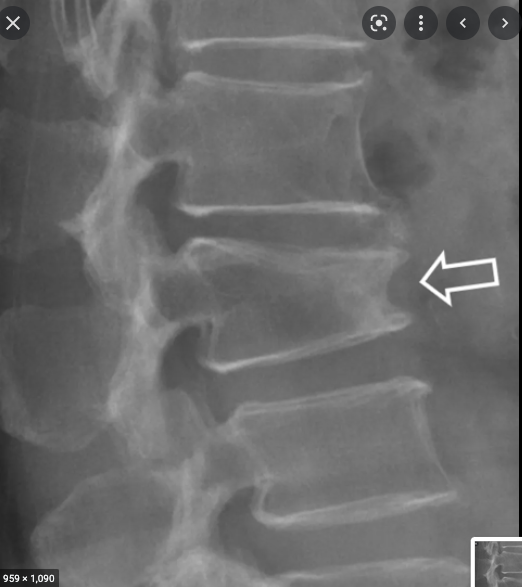

13

What is this?

Kyphotic deformity of the spine